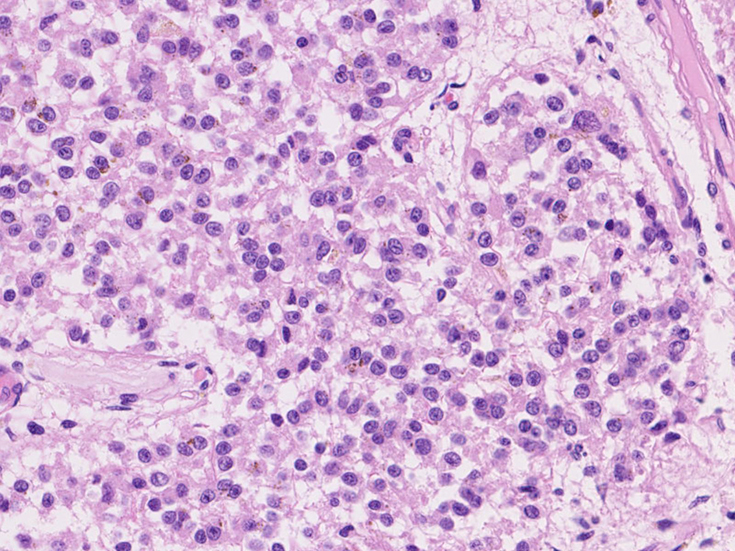

松果体の腫瘍 pinealoma

松果体には松果体の細胞またはその前駆細胞から発生する腫瘍の他に多くの腫瘍, glioma, meningiomaあるいは, 胚細胞腫germ cell tumorが発生する。

Pineal cell tumor 松果体細胞またはその前駆細胞より発生する。